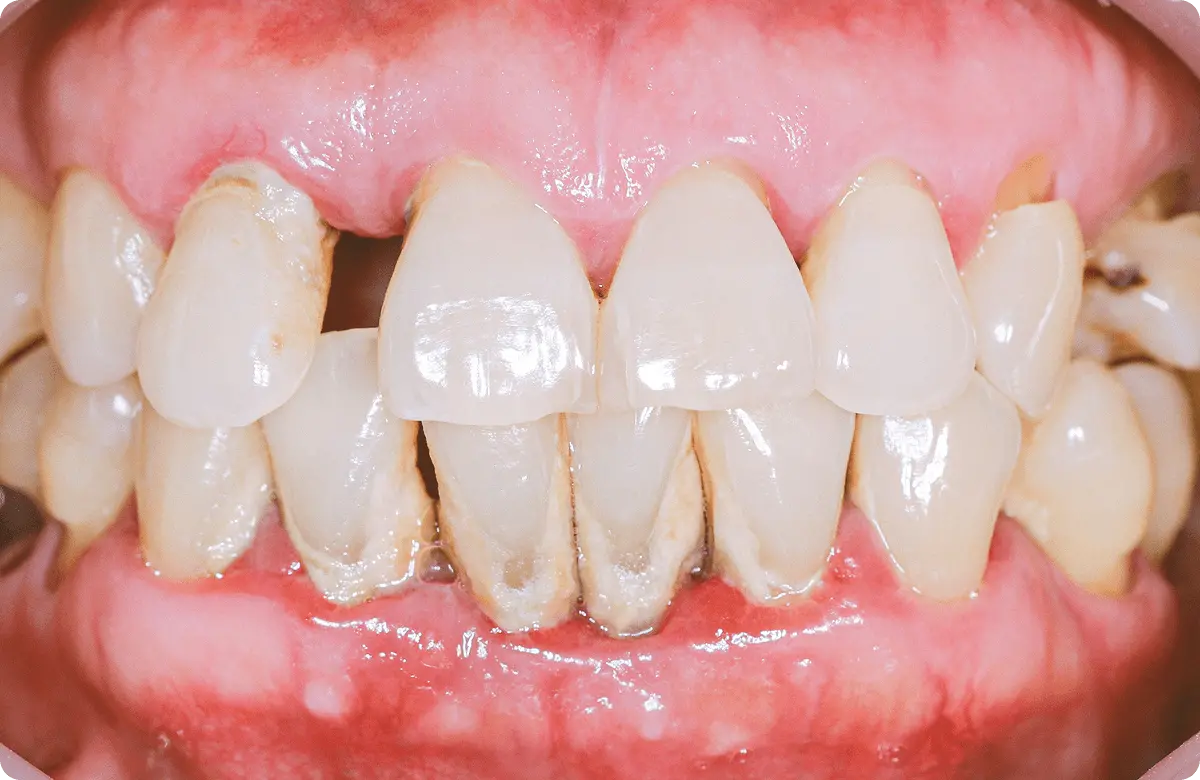

歯磨きをしなかったり、糖分などの栄養素が口の中に留まり続けると、細菌の塊が歯の周りに付着します。やがて細菌は毒素を出して歯ぐきを腫れさせたり、出血させたりします。このような症状を歯周病と言います。軽症の間は大きな痛みもなく気づかれることが少ないため「静かなる病」と言われることもあります。実際に、歯を失う最大の原因は歯周病という調査もあることから、気づかないうちに歯周病が進行していたということは珍しくありません。

歯垢は唾液などの成分によって数日で石のように硬い歯石へと変わります。歯石になると普段の歯ブラシで取り除くのはほぼ不可能で、ザラザラした表面がより多くの歯垢を付着させてしまいます。

口腔内写真

お口の中を撮る専用のカメラで適宜、撮影して記録をとります。ITeroという器械でスキャンデータを撮ることもあります。